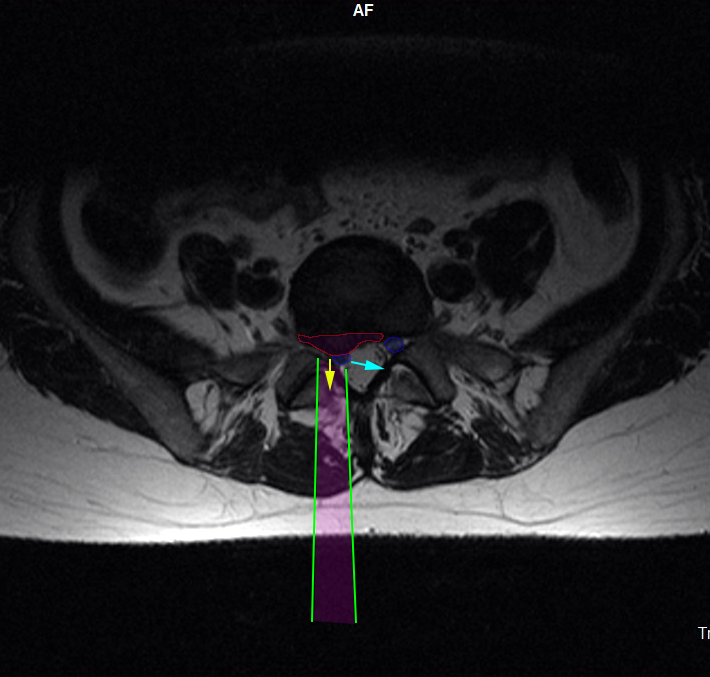

Η προσπέλαση (πράσινες γραμμές) της οσφυϊκής μικροχειρουργικής δισκεκτομής γίνεται με μικρή αποκόλληση των μυών της σπονδυλικής στήλης, διάνοιξη θυρίδας (οπής) στους συνδέσμους που καλύπτουν το νεύρο και σε ελάχιστο τμήμα του οσφυϊκού πετάλου. Το οσφυϊκό νεύρο (μπλέ) παρεκτοπίζεται και η κήλη (φούξια) αφαιρείται (κίτρινο βέλος). Όταν χρειάζεται, και από την ίδια προσπέλαση αφαιρείται και το περιεχόμενο του δίσκου, προκειμένου να επιτευχθεί πληρέστερη αποσυμπίεση του νεύρου.